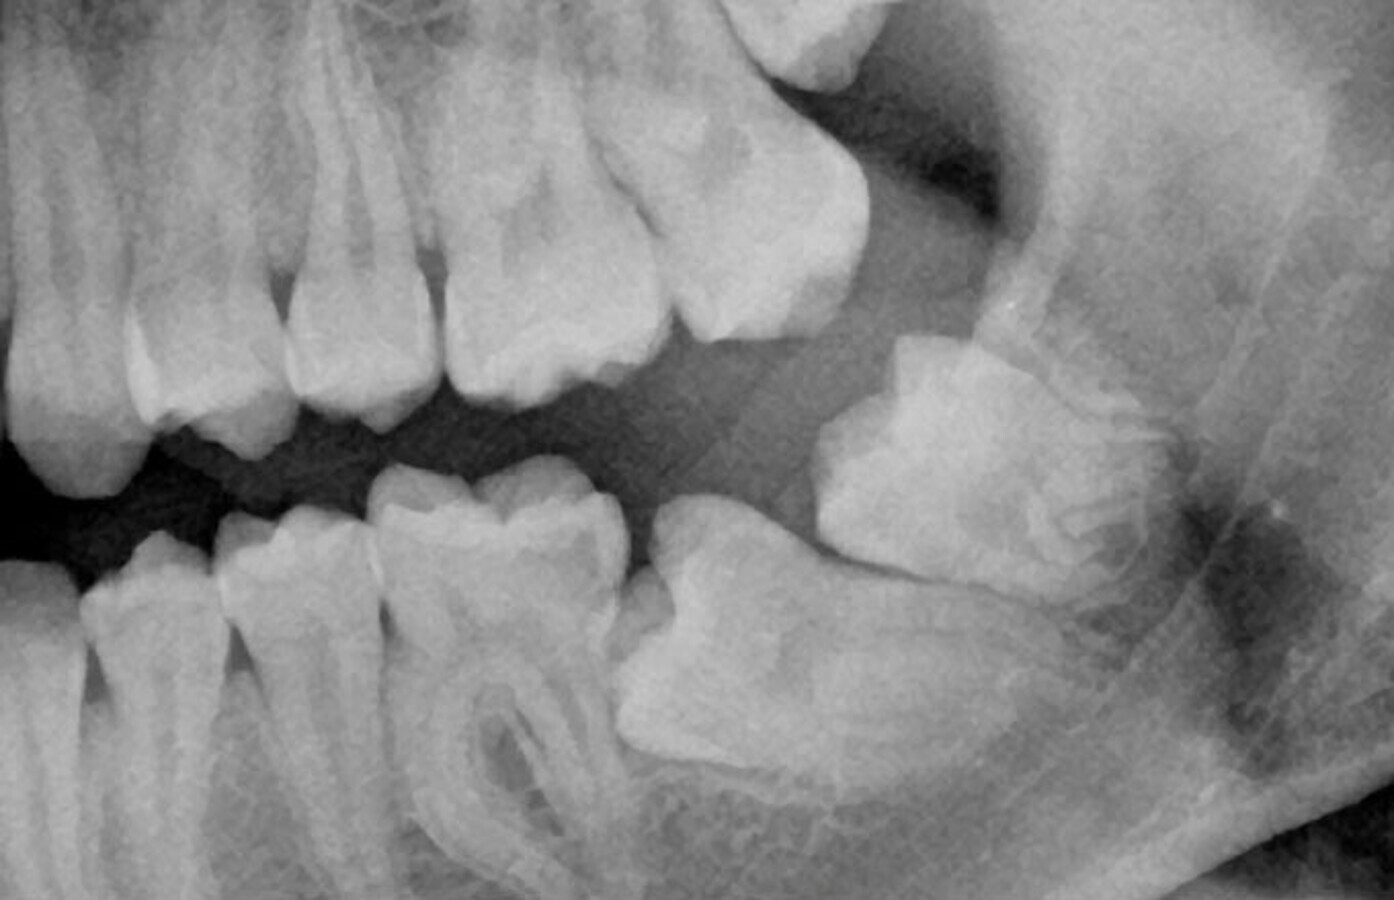

Rx de control tracción botón (final).

Aproximadamente 6 meses después, se prepara un anclaje esquelético con un tornillo de titanio autoperforante (D2.0 / L 12mm, Jeil Medical Corporation). Estos tornillos son más indicados para fijar injertos en bloque. Este anclaje permite enderezar el segundo molar por completo. En una primera fase, se tracciona desde el tornillo a un botón colocado en la cúspide distolingual del diente 37 con cadeneta elástica. Una vez el diente 37 está “desenclavado”, se termina de enderezar, cementando estratégicamente brackets y tubos de cementado directo y utilizando arcos elásticos NiTi.

Radiografía final.